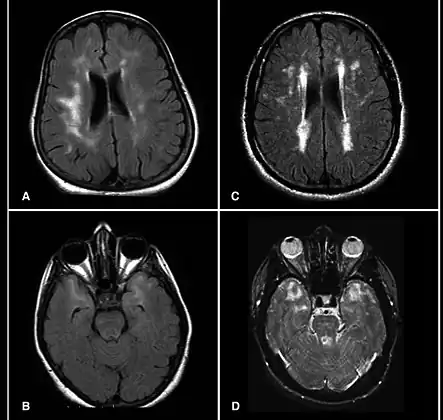

A hyperintensity or T2 hyperintensity is an area of high intensity on types of magnetic resonance imaging (MRI) scans of the brain of a human or of another mammal that reflect lesions produced largely by demyelination and axonal loss. These small regions of high intensity are observed on T2 weighted MRI images (typically created using 3D FLAIR) within cerebral white matter (white matter lesions, white matter hyperintensities or WMH)[1][2] or subcortical gray matter (gray matter hyperintensities or GMH). The volume and frequency is strongly associated with increasing age.[2] They are also seen in a number of neurological disorders and psychiatric illnesses. For example, deep white matter hyperintensities are 2.5 to 3 times more likely to occur in bipolar disorder and major depressive disorder than control subjects.[3][4] WMH volume, calculated as a potential diagnostic measure, has been shown to correlate to certain cognitive factors.[5] Hyperintensities appear as "bright signals" (bright areas) on an MRI image and the term "bright signal" is occasionally used as a synonym for a hyperintensity.

Hyperintensities are commonly divided into 3 types depending on the region of the brain where they are found. Deep white matter hyperintensities occur deep within white matter, periventricular white matter hyperintensities occur adjacent to the lateral ventricles and subcortical hyperintensities occur in the basal ganglia.